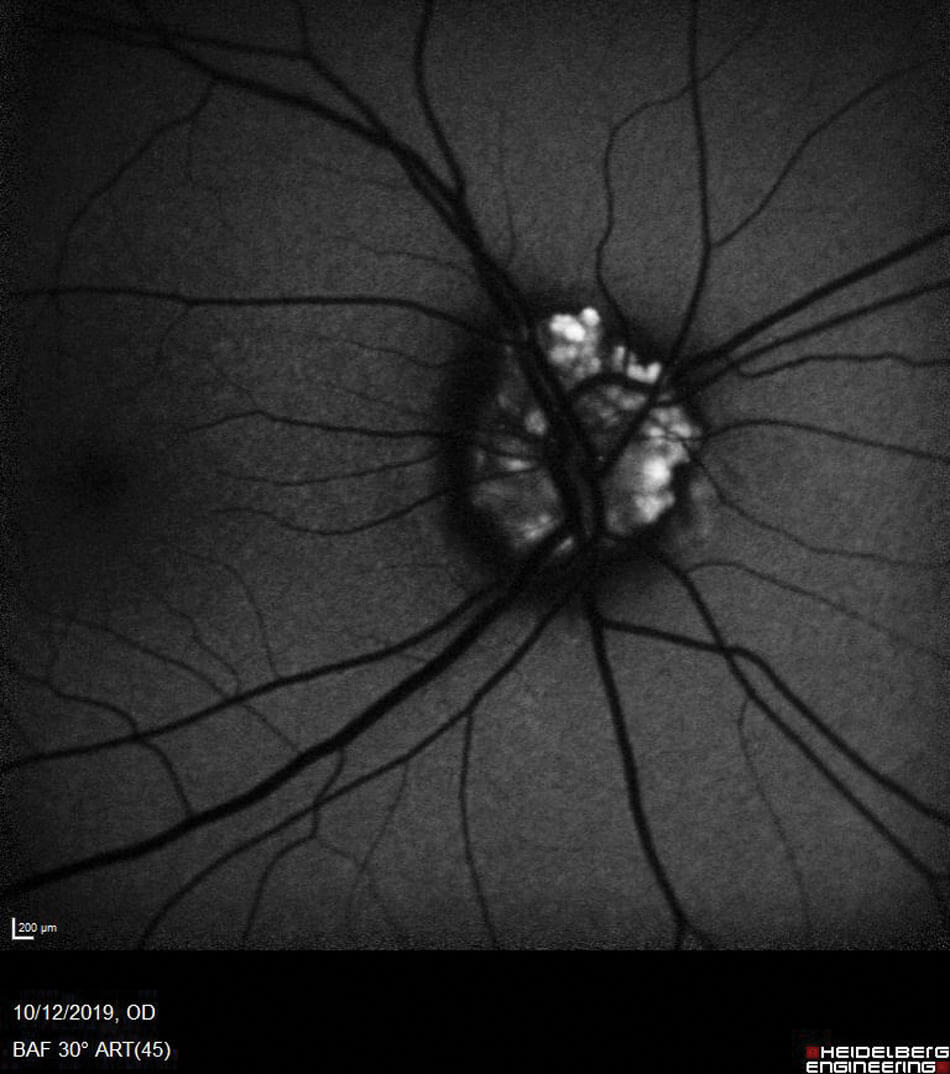

Optic disc drusen are congenital calcified hyaline abnormalities that occur within the disc. They can be superficial or buried and what type a patient has determines how easy it is to image them. Superficial disc drusen are easy to see on fundus examination and give the optic disc a bumpy and uneven appearance, as seen in Figure 4.

Because it is superficial we can use OCT to image within the disc. The initial scan best used is the optic nerve head scan, but with the setting amended to enhanced depth imaging (EDI). This causes the choroid to be the focus rather than the vitreous interface and therefore provides a clearer view of the drusen, as seen in Figure 5.In most cases these cause no problems, but it is important to be aware that some patients experience visual field defects because of the drusen, especially as they enter their 20s. In fact, I have only ever come across one case. Another way to image disc drusen is by using autofluorescence (FAF) imaging. Because of the make-up of disc drusen they give off a hypofluorescence, the level of which depends on how superficial or buried they are. Logically the more buried the drusen, the less hypofluorescent they are.

Figure 6: FAF showing superficial optic disc drusen.